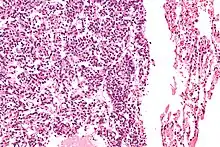

| Micrograph of a typical pulmonary carcinoid tumour. | |

The definitive diagnosis is rendered by a microscopic examination, after excision. Typical carcinoids have cells with stippled chromatin and a moderate quantity of cytoplasm. They typically have few mitoses and lack necrosis. By definition, they are greater than 4 mm in largest dimension; smaller lesions are referred to as pulmonary carcinoid tumourlets.

Very high magnification

With prominent rosettes